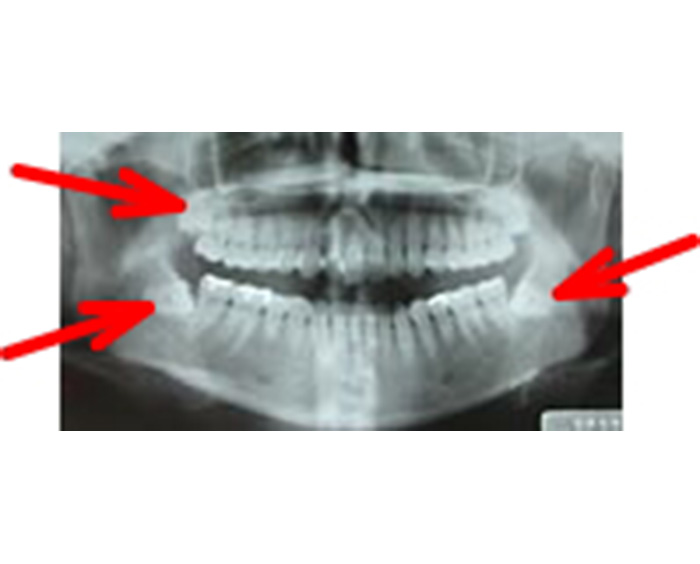

埋伏状智歯患者のオルソパントモ写真

左側下顎水平埋伏智歯

右側下顎水平埋伏智歯

左側下顎水平埋伏智歯施術後